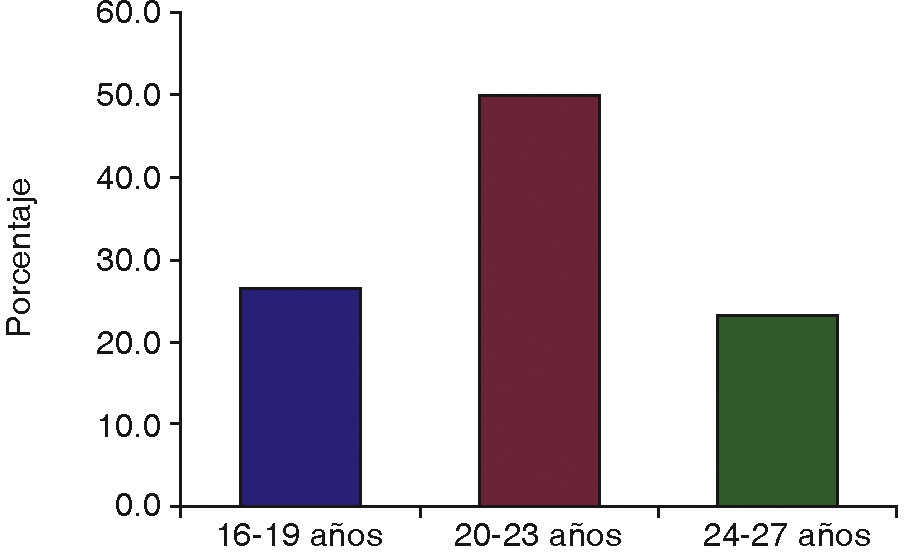

De los 30 pacientes incluidos en el estudio, 15 fueron del sexo femenino y 15 del sexo masculino. Fueron agrupados por edad, 8 pacientes de 16 a 19 años, 15 pacientes de 20 a 23 años, y 7 pacientes de 24 a 27 años (Figura 4). Se catalogaron por dificultad de extracción según la clasificación de Pederson17 en leve, moderada y muy compleja, con resultados de 7 leves, 22 moderadas y una muy compleja en el lado derecho y 8 leves, 20 moderadas y 2 muy complejas en el lado izquierdo (Figura 5).

La edad fue distribuida en tres grupos, de forma comparativa en la cicatrización de tejido óseo, los mejores valores medios se observaron para los grupos etarios del grupo experimental que para el grupo de control, y en cada caso el grupo de 20 a 23 años obtuvo el mejor valor.

El estudio demostró que la cicatrización de tejido blando y tejido óseo mejora con el uso de PRF, afirmando de esta manera su efectividad. Analizando por el grupo de edad, el de 20 a 23 años presentó mejor cicatrización de tejido óseo, comparado con el de 16 a 19 años que presentó el mejor resultado en cicatrización de tejido blando. Con relación al sexo masculino y femenino presentó mejor cicatrización el sexo masculino. Por último con respecto a la dificultad de extracción del tercer molar, no se vio influenciada la cicatrización en valores significativos, tanto en casos complejos, de mediana complejidad o en los que la cirugía se tornó rápida y fácil.